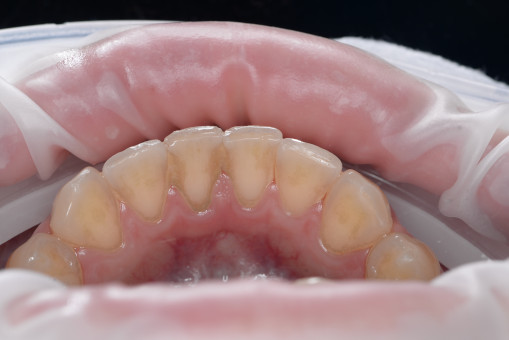

А прежде, чем вы посмотрите фотографии «до» и «после» лечения слизистой оболочки полости рта, проведенных в нашей клинике, хочу поблагодарить большое количество наших пациентов, которые поверили, прониклись нашей концепцией, и мы вместе, именно вместе победили болезни десны, гингивит и пародонтит!

До/после лечения